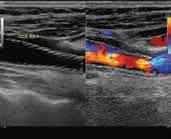

С карактеристикама ултразвучних таласа већ смо вас упознали. Можемо

поновити да су то механички лонгитудинални таласи чије се фреквенције налазе

у подручју од 20 000 Hz до 109 Hz. За људско ухо ултразвучни таласи су нечујни. Због веће фреквенције носе и већу енергију од

таласа које чујемо.

Управо због велике продорности и интеракције с материјалном средином (ткивом) ултразвук је

али и у терапији и хирургији. Приликом проласка

1. континуирани ултразвучни

2.

3. колор-доплер.

Континуирани